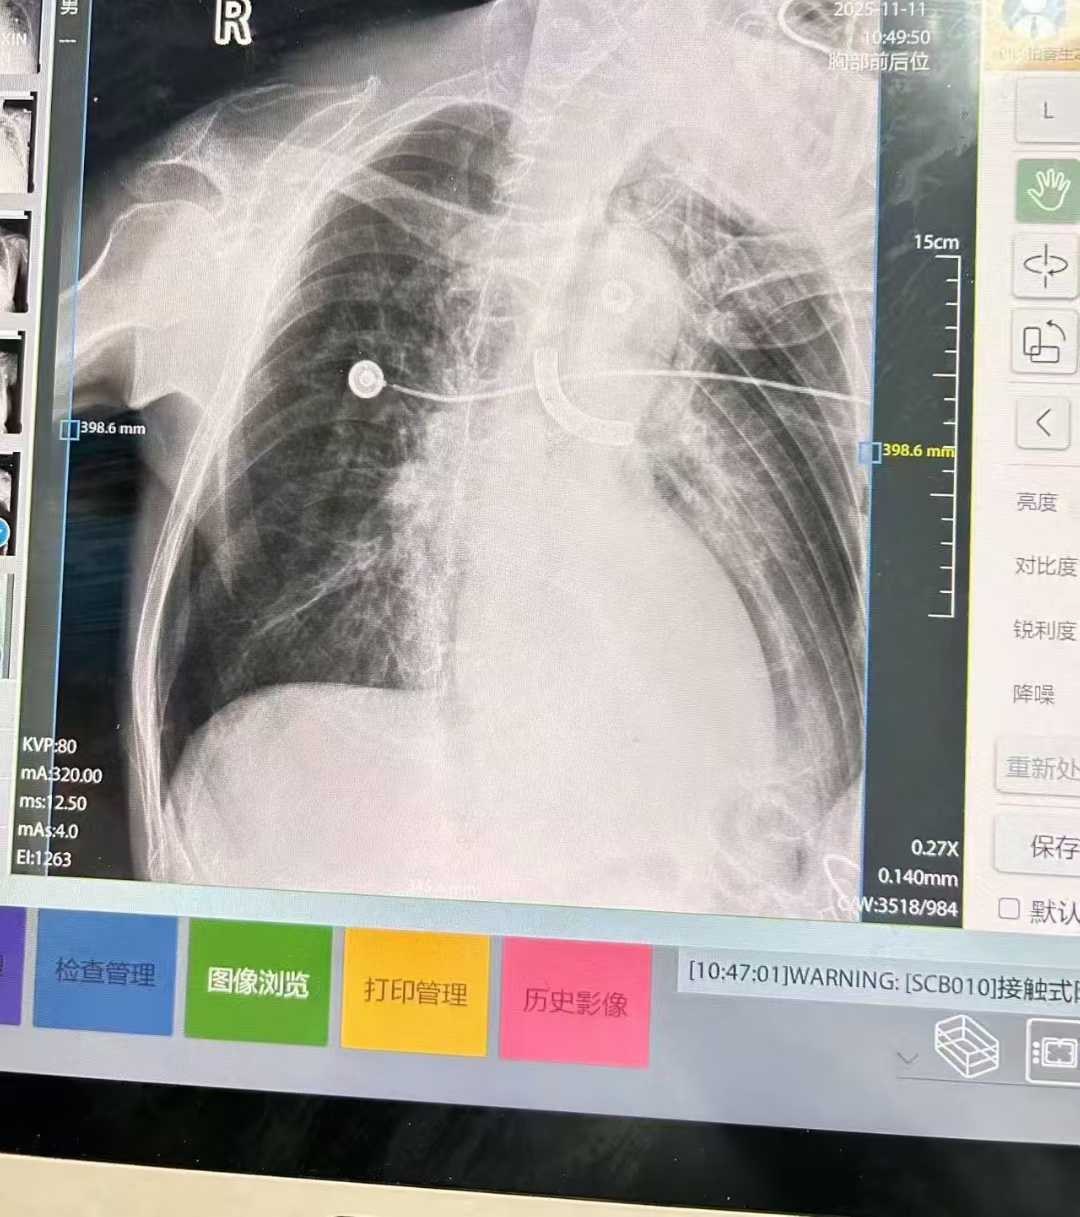

患者柏先生今年73岁,因长期留置气切套管,此次突发呼吸困难,被养老院工作人员发现气管套管脱落至气管内。当天早上8时40分,南溪山医院急诊科迅速联系呼吸与危重症医学科二病区预留床位,并将患者紧急转至病区救治。入院后,吴娟主任医师、李海斌副主任医师联合内镜中心团队立即开展床边支气管镜探查。在多次尝试以异物钳夹取异物未果、异物无法通过声门的情况下,呼吸二病区团队迅速启动应急预案,联系麻醉科团队,改为急诊硬质支气管镜手术取出异物。术中,异物随硬镜一同被顺利取出,从插入硬镜到取出异物仅用时数分钟。12时30分,手术顺利结束,患者安全病房。术后,患者咳嗽、气喘等症状明显改善,充分体现了南溪山医院呼吸与危重症医学科高效的急诊救治能力。

呼吸二病区屈东明主任指出,气道内异物是呼吸科常见的急危重症,若处理不及时,可能迅速导致患者窒息,危及生命。南溪山医院开展的硬质支气管镜手术,能够迅速、有效地解决气道异物堵塞问题,为患者争取宝贵的救治时间。